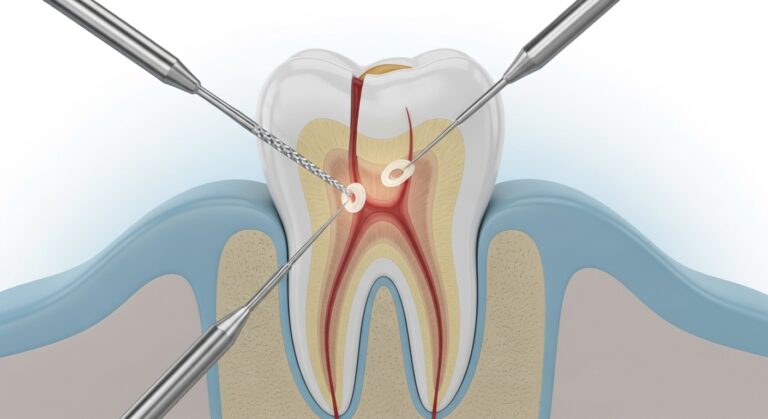

Introduction Endodontics is the branch of dentistry that deals with diseases of the tooth’s pulp, which is located in the center…